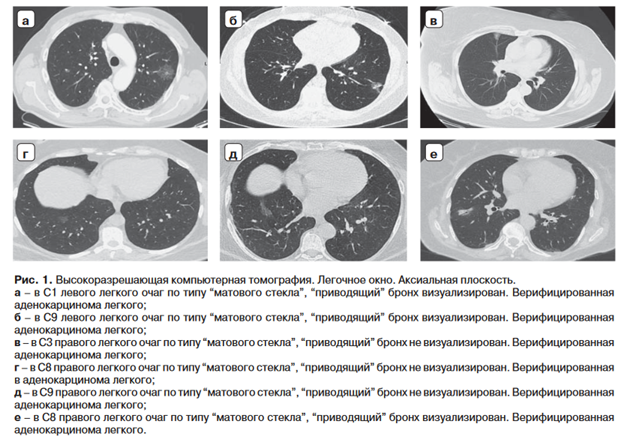

На первом этапе пациентам из обеих групп проведена КТн с целью определения визуализации “приводящего” бронха (рис. 1).

У 21 (65,6%) из 32 пациентов из основной группы визуализировался “приводящий” к очагу бронх. Не визуализирован у 11 (34,3%). У 21 (55,2%) из 38 пациентов контрольной группы визуализировался “приводящий” к очагу бронх. Не визуализирован у 17 (44,7%) (табл. 1).